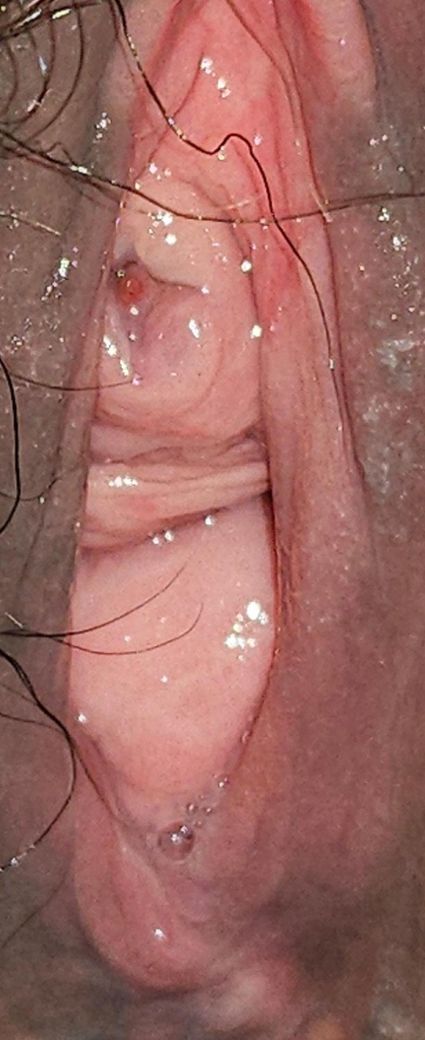

네번째 사진은 지금 사진이에요 점상출혈처럼 보여요 (피는 안묻어나고 집에있던 소뵨검사로 잠혈도 안나왔어요)

이 병변은 전형적인 “덩어리형 카룬클”은 아니지만, 카룬클 스펙트럼에 포함되는 요도 점막 취약 병변으로 해석하는 것이 가장 합리적입니다. 중심부에 작은 미란과 국소 출혈 흔적이 있고, 주변 점막은 창백하면서 얇고 광택이 있으며 주름이 줄어든 모습입니다. 이는 에스트로겐 저하로 인한 요도 점막 위축 상태에서 흔히 보이는 소견입니다.

중앙의 붉은 점은 점상출혈 또는 표재성 미란으로 보이며, 종괴성 증식, 불규칙한 경계, 단단한 침윤 소견은 관찰되지 않습니다. 즉 악성 병변이나 요도암을 시사하는 형태는 아닙니다. 실제로 출혈이 묻어나지 않고 소변검사 잠혈이 음성인 점도 이를 뒷받침합니다.

처음 보였던 “뾰루지처럼 튀어나온 병변”은 초기 국소 점막 탈출 또는 염증성 부종이었을 가능성이 높고, 에스트로겐 연고 사용 후 부피는 줄었지만 혈관이 표재화되면서 지금처럼 빨갛게 보이는 단계로 넘어온 것으로 설명됩니다. 이 과정에서 카룬클처럼 보였다가, 현재는 “아무것도 아닌 것처럼” 보일 수 있습니다. 그래서 의료진 간 설명이 달라진 것입니다.